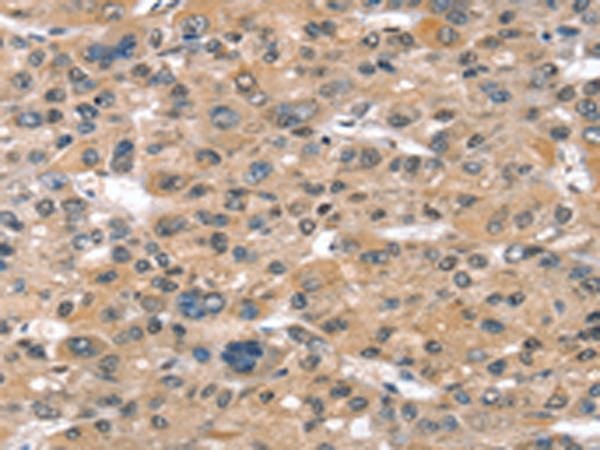

分类: 科研抗体货号: P08819别名: ST1B1; ST1B2; SULT1B2应用: WB,IHC反应种属: Human